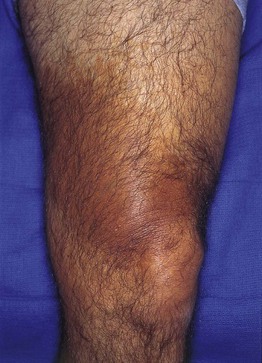

Fig. 92.5 Becker's nevus. Large patch of hyperpigmentation on the leg, which is medium brown in color. These lesions may be misdiagnosed as café-au-lait macules or congenital melanocytic nevi, especially when they do not occur on the upper trunk. Courtesy, Jean L. Bolognia, MD.